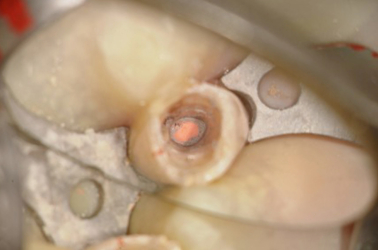

Rotary at End of Root, Note GP in File and Bacteria on GP

Close Up View of GP and Rotary File

GP Fragments in Canal at High Mag

Note Small Amount of GP in Canal Under Scope